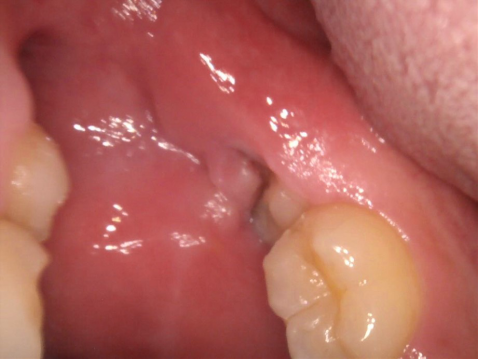

1.上も下も親知らずが半分しか頭を出さず、その周りに磨き残しが出来てしまいます

親知らずに歯肉がかぶさり、ブラッシングが思うように出来ません。虫歯と歯槽膿漏になる可能性が高くなります。

前の歯の陰に隠れて親知らずまで歯ブラシが届かず、汚れがいっぱい残っています。